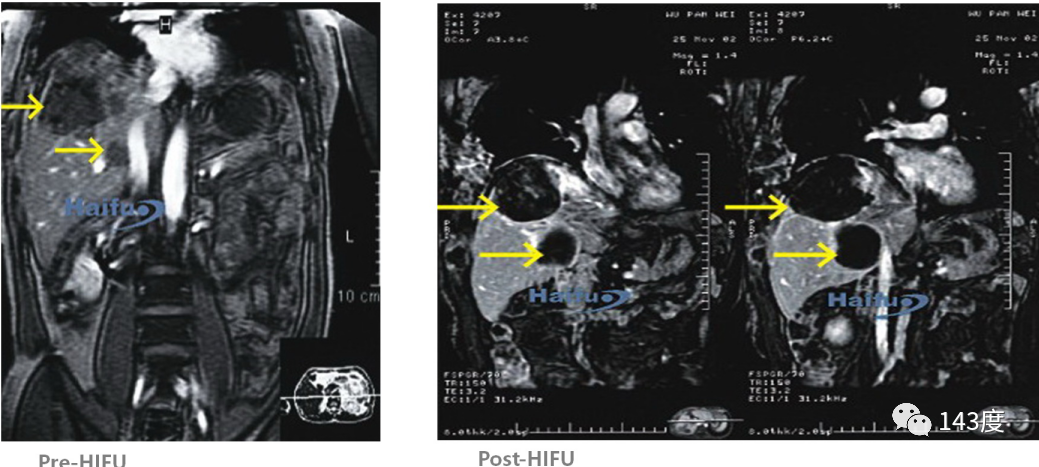

Liver Cancer Treatment Case 6:

Patient: Female, 70 years old, primary liver cancer

Highly vascular tumor measuring 120mm * 100mm found in the right lobe of the liver. Complete tumor ablation achieved after HIFU treatment, gradually absorbed over time.